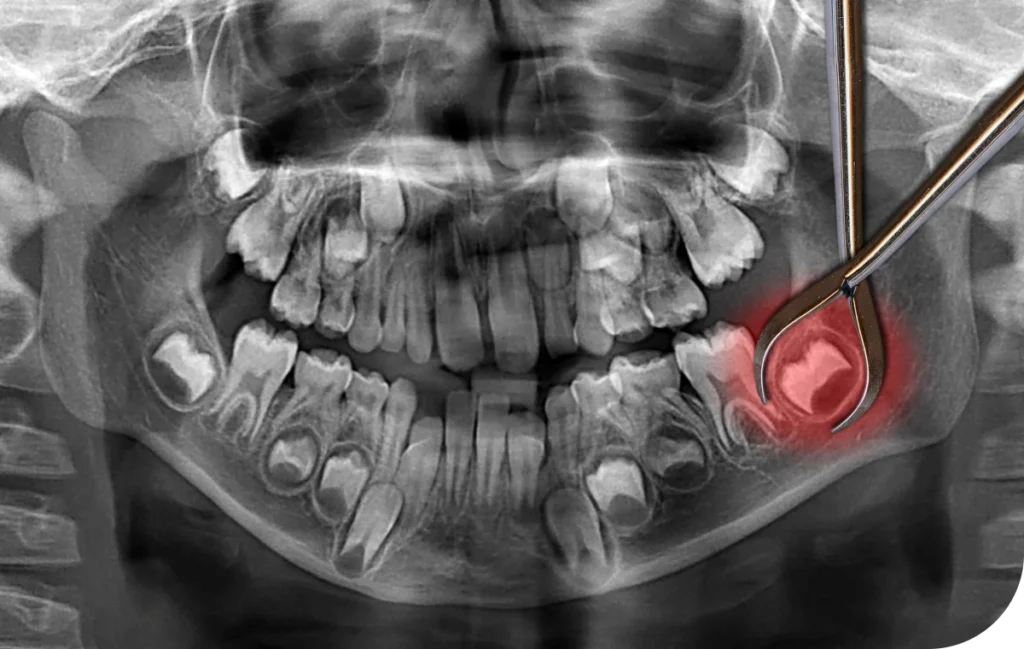

Les dents incluses posent fréquemment des problèmes, notamment lorsqu’elles concernent les troisièmes molaires. Ces dents peuvent rester bloquées sous la gencive ou émerger partiellement. Dans bien des cas, leur extraction devient indispensable. Ce geste chirurgical, courant en cabinet dentaire, permet d’éviter infections, douleurs chroniques ou déplacements dentaires.

Une dent est dite incluse lorsqu’elle ne parvient pas à percer complètement la gencive. Cette situation touche le plus souvent les dents de sagesse, qui apparaissent à l’âge adulte. Lorsqu’elles restent coincées ou se développent de manière oblique, elles peuvent provoquer des douleurs, des inflammations ou même perturber l’alignement des dents voisines.

Par ailleurs, une dent incluse peut rester silencieuse pendant des années. Pourtant, une infection peut se déclarer soudainement, ou un kyste peut se former autour de la dent. Dans ces cas, une intervention devient incontournable. Le praticien propose alors une extraction, soit curative, soit préventive, selon les signes cliniques et radiologiques.

L’intervention suit un protocole rigoureux. Elle commence toujours par une consultation pré-opératoire. Lors de ce rendez-vous, le praticien effectue un examen de la cavité buccale et analyse les clichés radiographiques. Cela lui permet de localiser précisément la dent incluse, d’évaluer sa proximité avec les nerfs ou les sinus, et de planifier l’acte chirurgical avec précision.

Le jour de l’intervention, l’anesthésie locale est généralement suffisante. Elle permet au patient de rester conscient tout en bloquant la douleur. Une fois la zone insensibilisée, le chirurgien incise la gencive pour accéder à la dent. Dans certains cas, il retire un peu d’os afin de dégager la couronne. Si l’extraction s’avère difficile, la dent est découpée en plusieurs fragments. Après le retrait, la plaie est nettoyée, puis suturée.